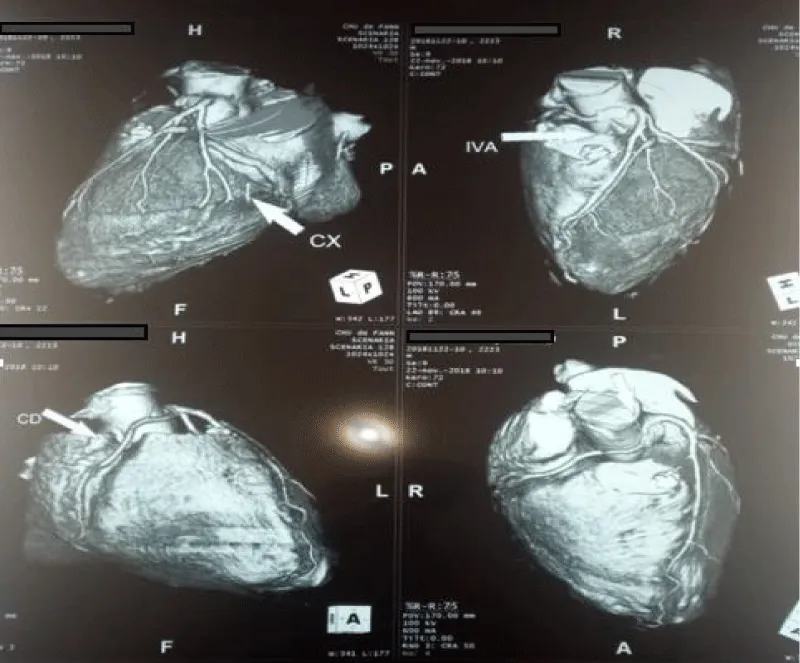

A coronarography was performed, showing an angiographically normal left mesh; the RCA was not visualized. The CT scan found a birth and RCA path abnormality describing an aortopulmonary path (Figure 3). Stress ultrasound was negative. Clinical monitoring has been proposed.

Download Image

Figure 3: Anomaly of birth and path of the right coronary artery describing an aortopulmonary path.